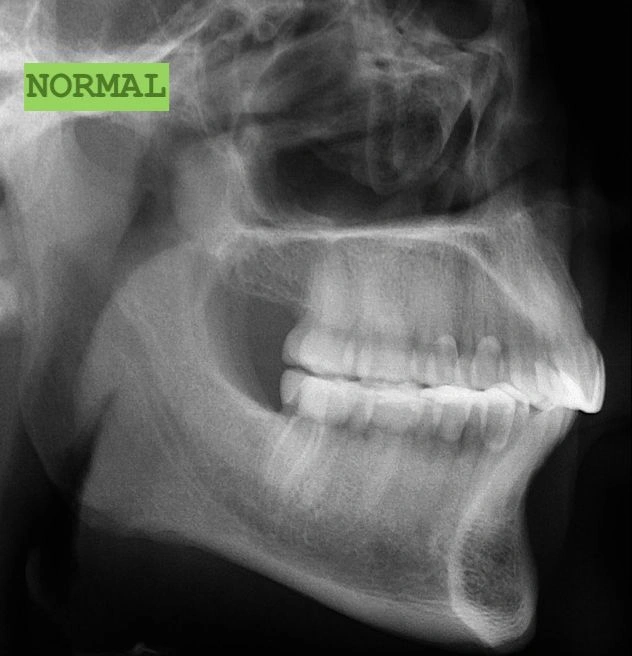

2. The Underbite: When the Upper Teeth Are Behind the Lower Teeth

Another common issue is an underbite. This is a horizontal problem where the lower teeth are pushed out past the upper teeth.

Visual Example:

Example #1 (young adult):